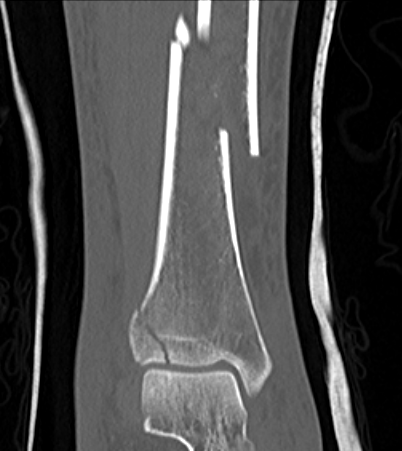

Posterior Malleolar Fractures

- occult in 70%

- especially with spiral distal tibial fractures

Posterior malleolar fixation

Typically stabilize intra-articular fracture first